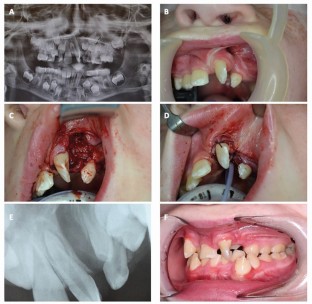

Primary cleft surgery refers to the planned surgical procedure(s) necessary to reconstruct an orofacial defect according to a specified protocol; in the context of a unilateral cleft lip and palate, this would include lip repair (with vomer flap closure of the hard palate), subsequent repair of the residual soft palate cleft and finally, the alveolar bone graft. This paper will provide an overview of the goals of primary surgical reconstruction, including the utility of pre-surgical orthopaedic techniques, including nasoalveolar moulding. The surgical methods of primary lip repair in both unilateral and bilateral clefts will be outlined and the concept of a primary rhinoplasty will be introduced. The principal techniques of cleft palate reconstruction will be delineated for a variety of cleft phenotypes. The final element of the primary reconstructive sequence is the alveolar bone graft using cancellous bone harvested from the iliac crest at approximately 8-10 years of age. The role of optimising oral hygiene prior to bone grafting cannot be over-emphasised and the utility of pre-surgical orthodontic arch expansion is also discussed. In the UK, bone graft outcomes are audited using the Kindelan score, which is evaluated from the six-month postoperative upper standard occlusal radiograph.

Kindelan J D, Nashed R R, Bromige M R. Radiographic assessment of secondary autogenous alveolar bone grafting in cleft lip and palate patients. Cleft Palate Craniofac J 1997; 34: 195-198.

Coots B K. Alveolar bone grafting: past, present, and new horizons. Semin Plast Surg 2012; 26: 178-183.